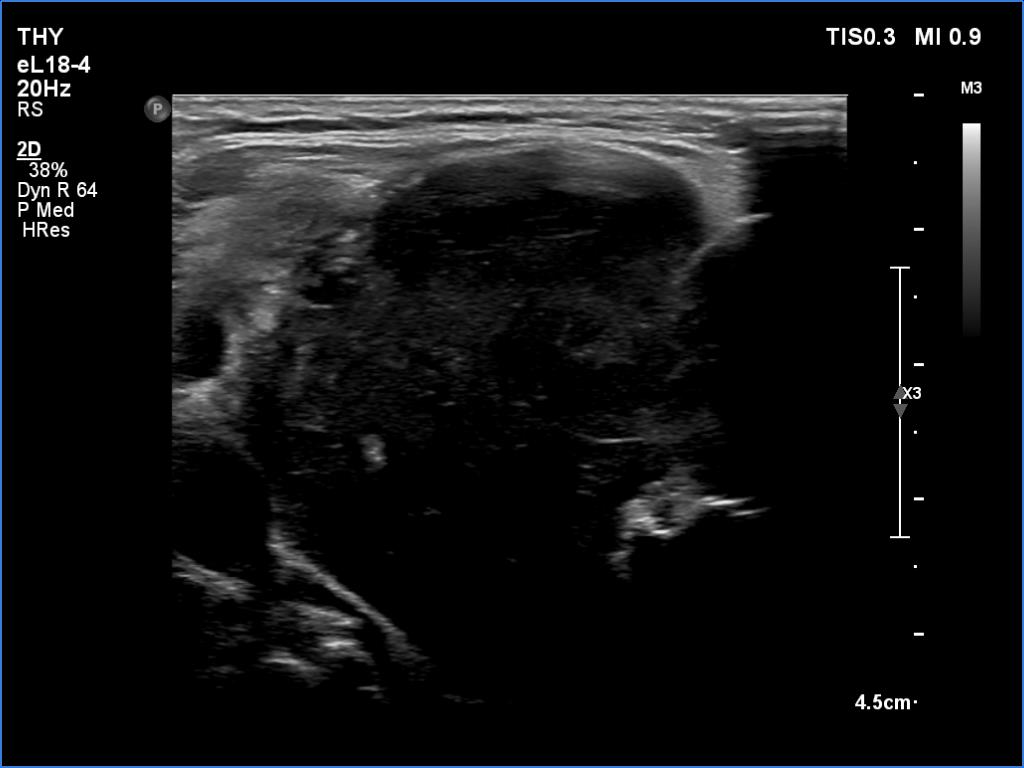

Thyroid cancers - case 1174 (ultrasonographic picture 3)

Right lobe, another transverse view - with more harmonization. By using this setting, it is impossible to differentiate between cystic and deeply hypoechoic structures.